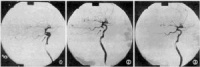

耳长期持续流脓,有特殊恶臭鼓膜松弛部或紧张部后上方有边缘性穿孔(图9-3)。从穿孔处可见鼓室内有灰白色鳞屑状或豆渣样物质,奇臭(耳部彩图10,11)。一般有较重传导

性聋,如病变波及耳蜗耳聋呈混合性。乳突X线摄片示上鼓室、鼓窦或乳突有骨质破坏区,边缘多浓密、整齐。

又称坏死型或肉芽型,多由急性坏死型中耳炎迁延而来。组织破坏较广泛,病变深达骨质,听小骨、鼓窦周围组织可发生坏死;粘膜上皮破坏后,局部有肉芽组织或息肉形成。此型特点:耳流脓多为持续性,脓性间有血丝,常有臭味。鼓膜紧张部大穿孔可累及鼓环或边缘性穿孔。鼓室内有肉芽或息肉,并可经穿孔突于外耳道。传导性聋较重。乳突X线摄片为硬化型或板障型,伴有骨质缺损破坏。

胆脂瘤非真性肿瘤,而为一位于中耳、乳突腔内的囊性结构。囊的内壁为复层鳞状上皮,囊内充满脱落上皮、角化物质及胆固醇结晶,囊外侧以一层厚薄不一的纤维组织与其邻近的骨壁或组织紧密相连。由于囊内含有胆固醇结晶,故称胆脂瘤(cholesteatoma)。